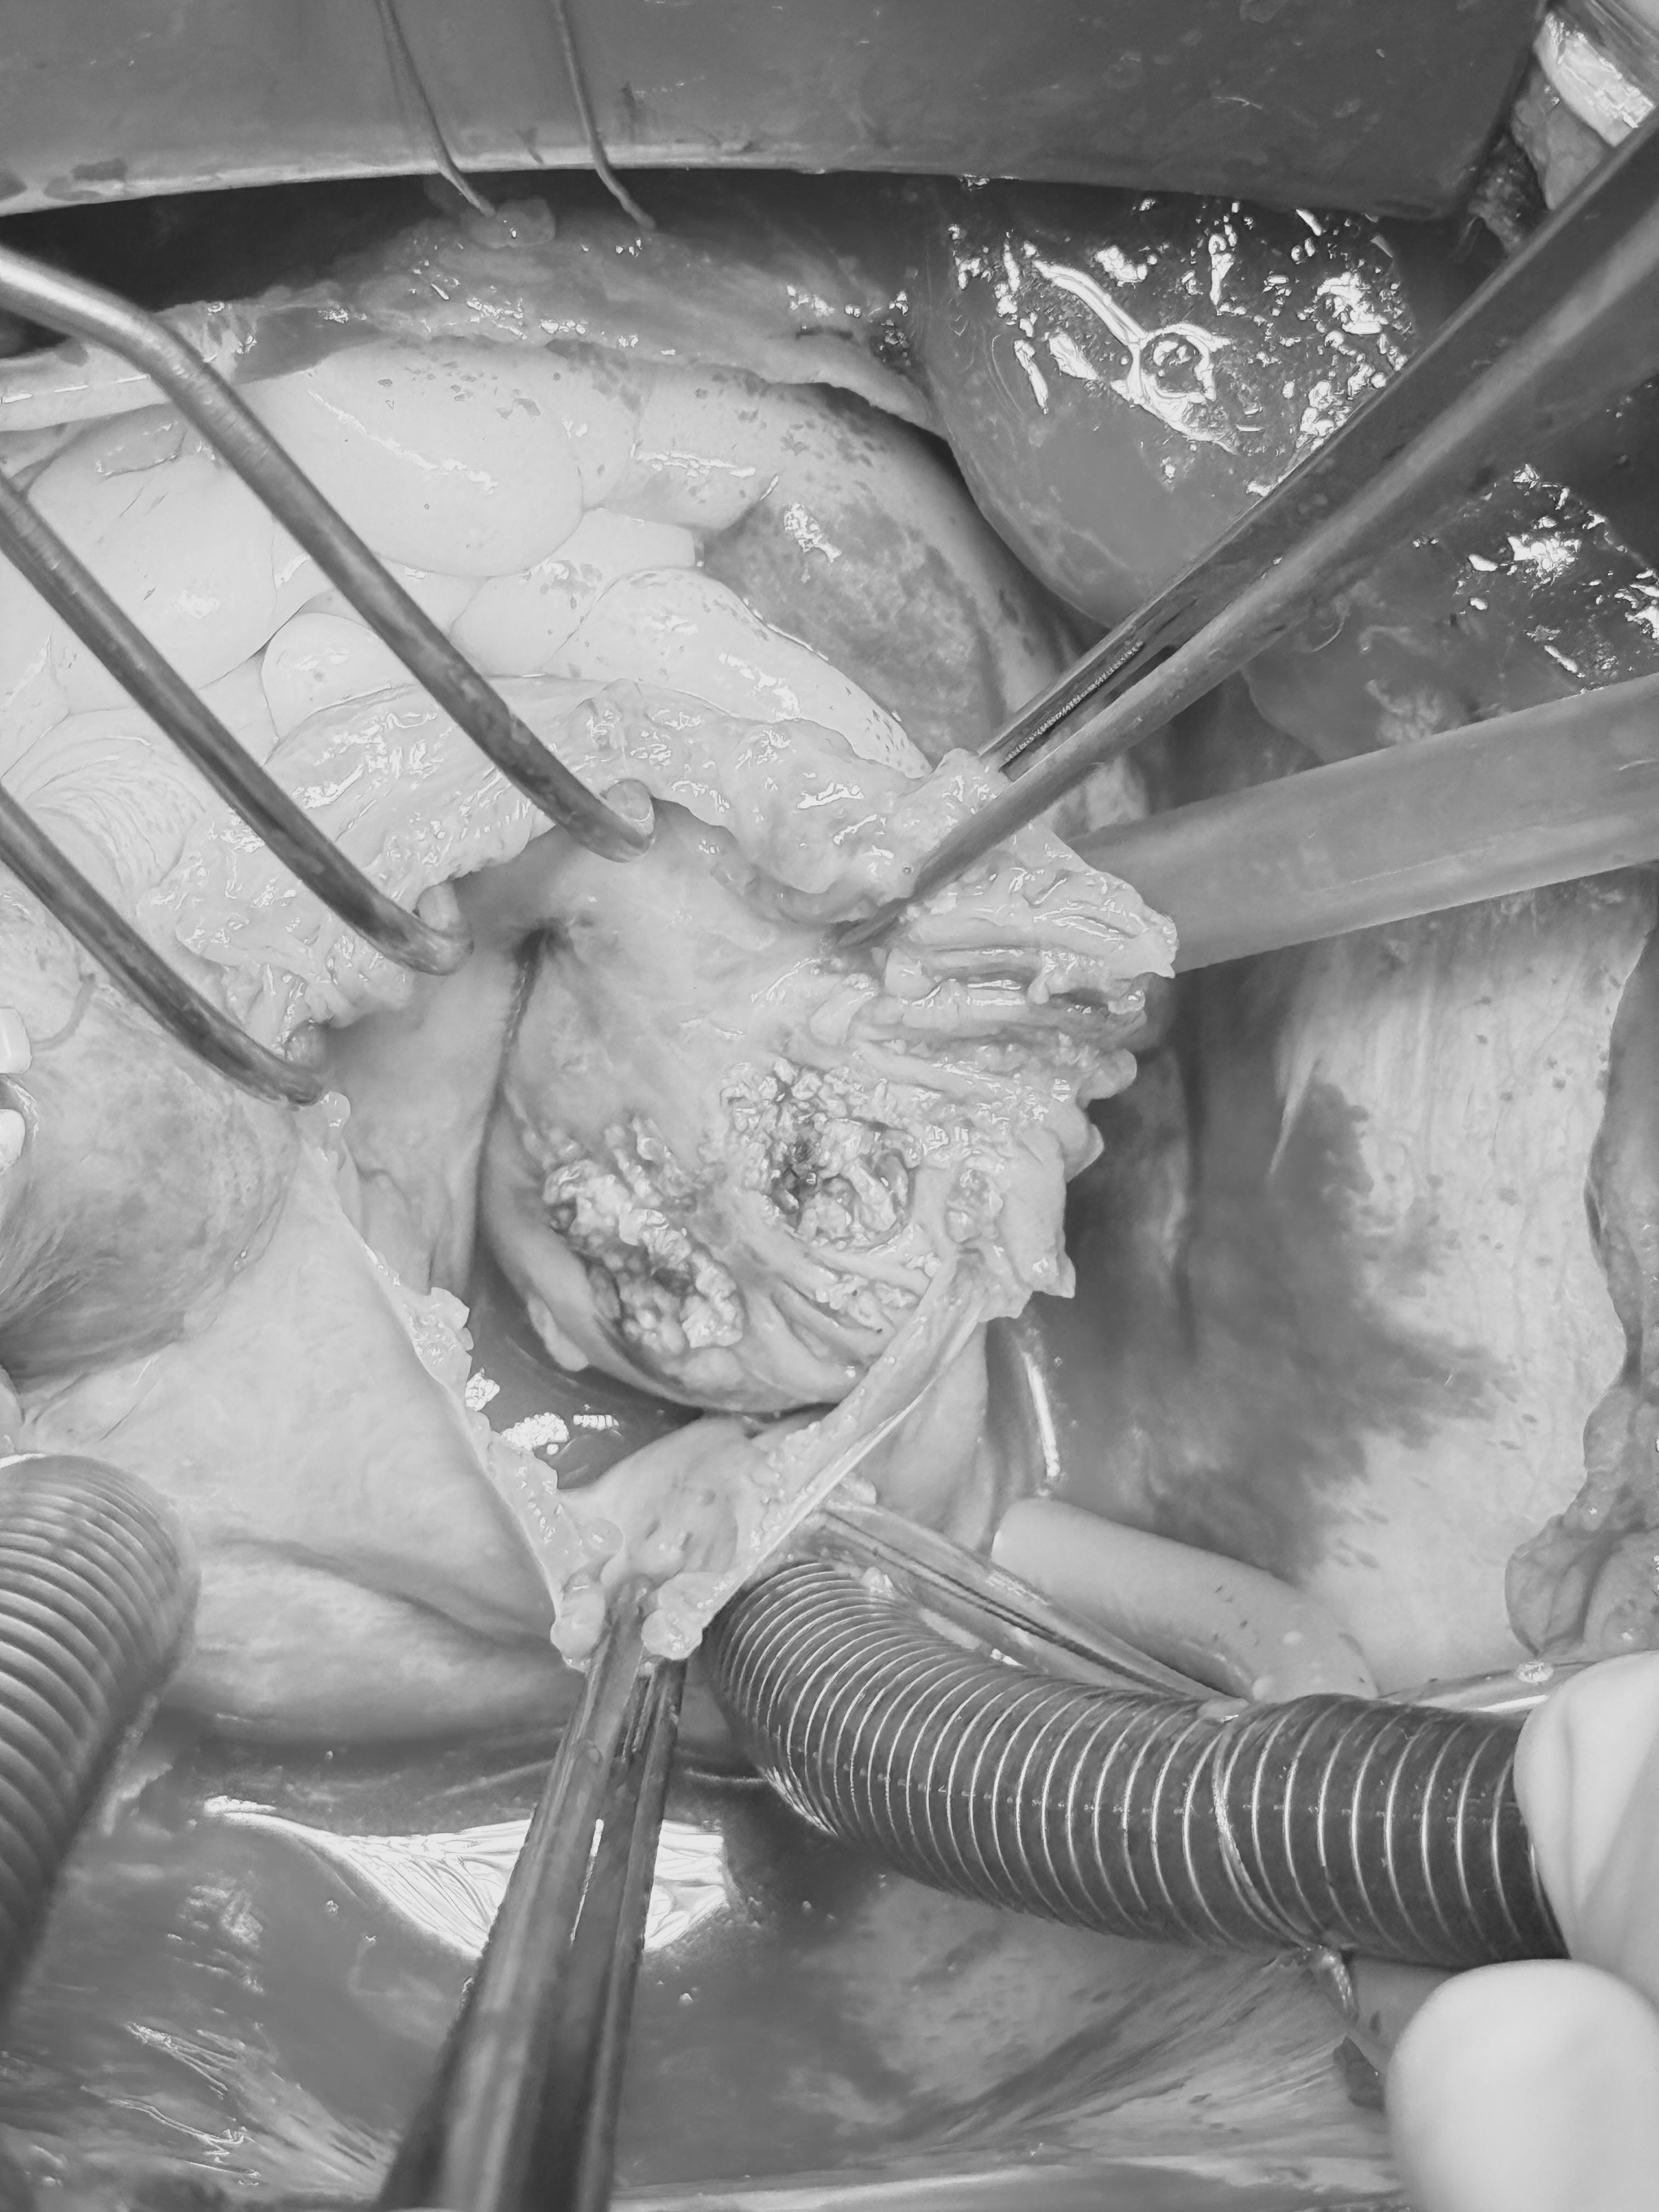

Ашыгыч медицина ярдәме хастаханәсе кардиохирурглары нечкә, ювелир эш башкарганнар. Табиблар пациентка йөрәгендәге яңа шешне алганнар, ә аннары махсус криозонд кулланганнар. Бу тере тукымаларны туңдыру коралы. Зарарланган өлкәгә, шеш киселгән урыннарда, хирурглар түбән температуралар (-70 °C кадәр) белән тәэсир иткәннәр. Бу шешнең алга таба үсүенә юл куймау өчен эшләнә. Алганнан соң материалны гистологиягә җибәргәннәр. Шеш яман булып чыкмаган.

Операция катлаулы булды, ләкин безнең хирурглар шешне тулысынча  ала алды. Хәзер хатын-кыз хастаханәдән чыгарылган һәм гаиләсе һәм якыннары даирәсендә.